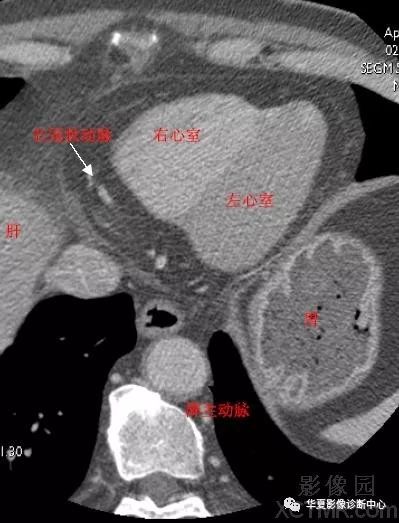

心脏CT解剖图解

心脏CT解剖图解,心脏ct解剖图

心脏冠状动脉ct解剖中文详细标注图文

影像解剖|心脏冠状动脉ct解剖中文详细标注(图文)

心脏冠状动脉ct解剖中文详细标注(图文)

心脏的这些ct切面图像你都能识别吗

心脏冠状动脉ct解剖中文详细标注(图文)cardiacanatomy